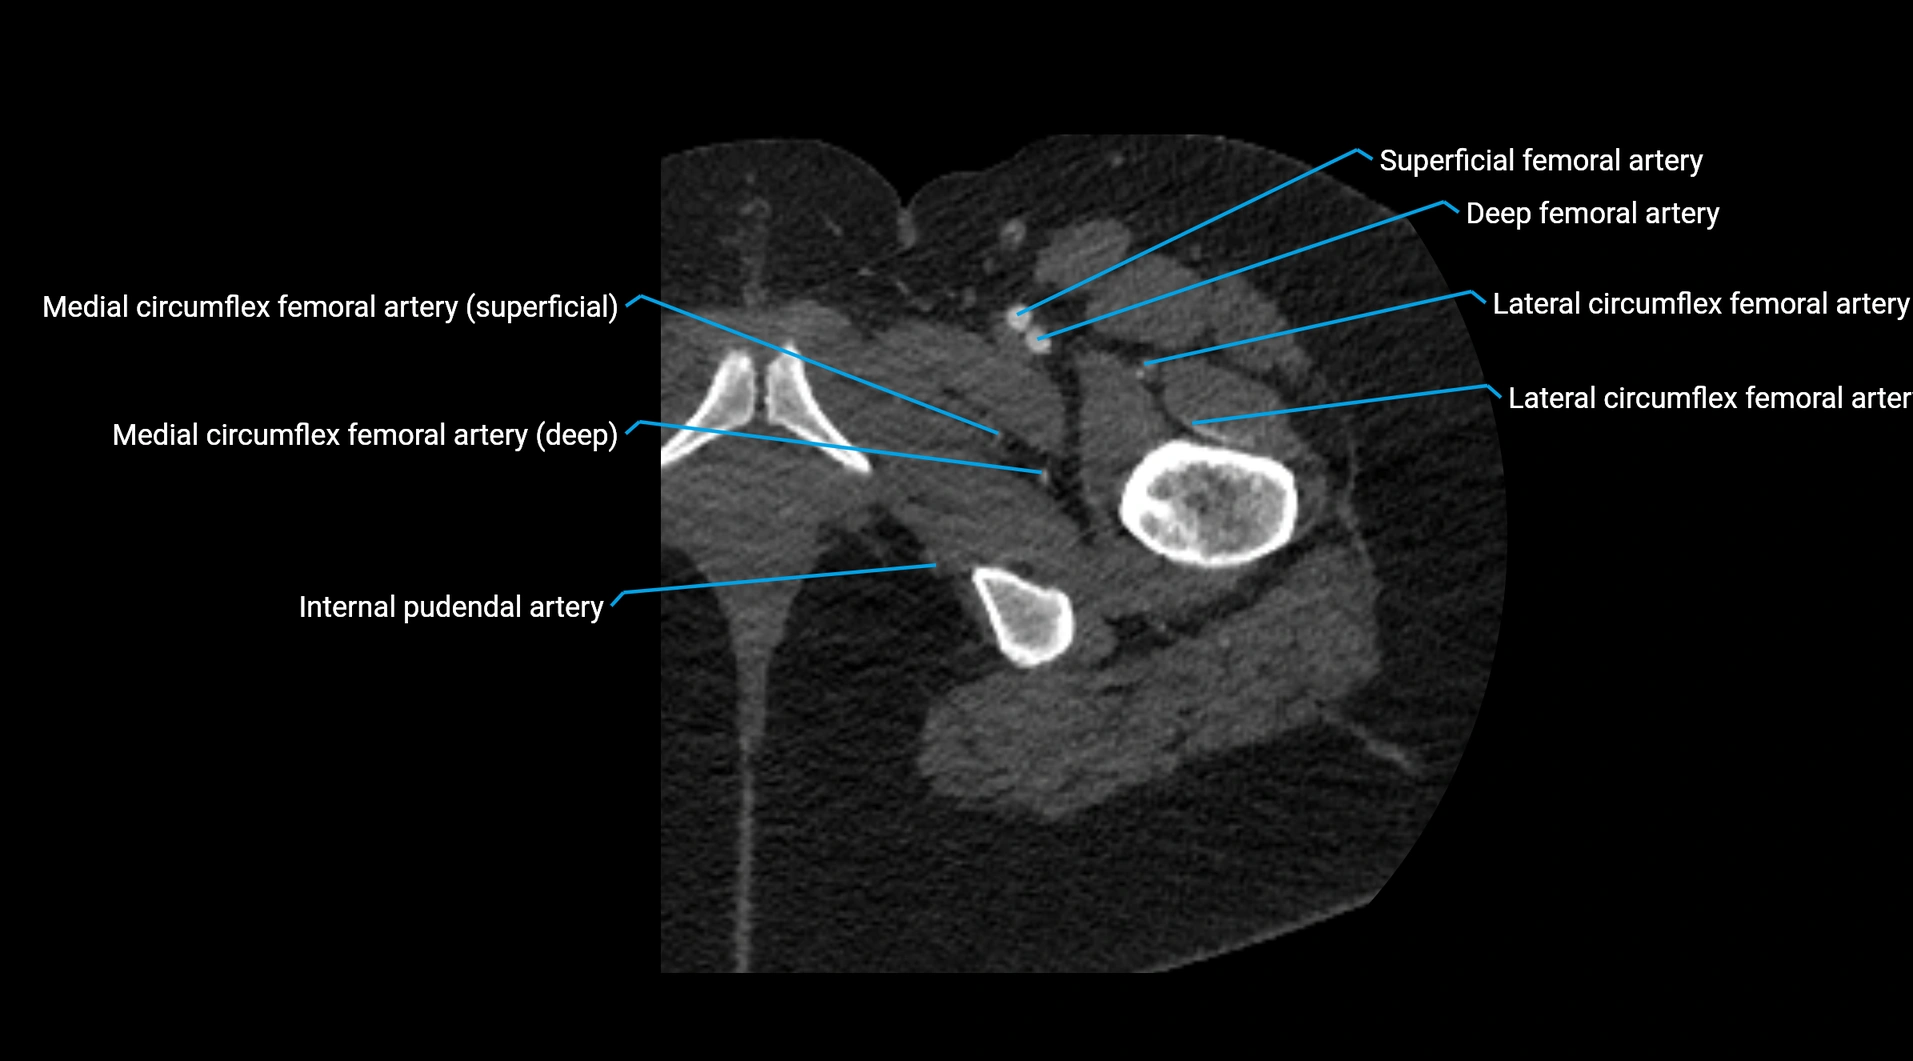

CT images

image

Contrast-enhanced CT (CTA):

• Gold standard for abdominal aortic imaging

• Provides excellent detail of lumen, wall, aneurysm, thrombus, and branch vessels

• Multiplanar and 3D reconstructions help in aneurysm measurement, stent graft planning, and dissection evaluation